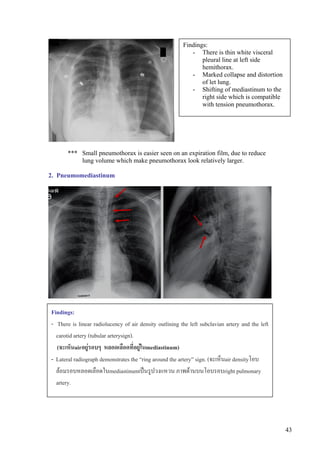

1.2 Tension pneumothorax:

Findings:

- There is thin white visceral

pleural line at left side

hemithorax.

- Marked collapse and distortion

of let lung.

- Shifting of mediastinum to the

right side which is compatible

with tension pneumothorax.

*** Small pneumothorax is easier seen on an expiration film, due to reduce

lung volume which make pneumothorax look relatively larger.

2. Pneumomediastinum

- There is linear radiolucency of air density outlining the left subclavian artery and the left

carotid artery (tubular arterysign).

(จะเห็นairอยูรอบๆ หลอดเลือดที่อยูในmediastinum)

- Lateral radiograph demonstrates the “ring around the artery” sign. (จะเห็นair densityโอบ

ลอมรอบหลอดเลือดในmediastinumเปนรูปวงแหวน ภาพดานบนโอบรอบright pulmonary

artery.